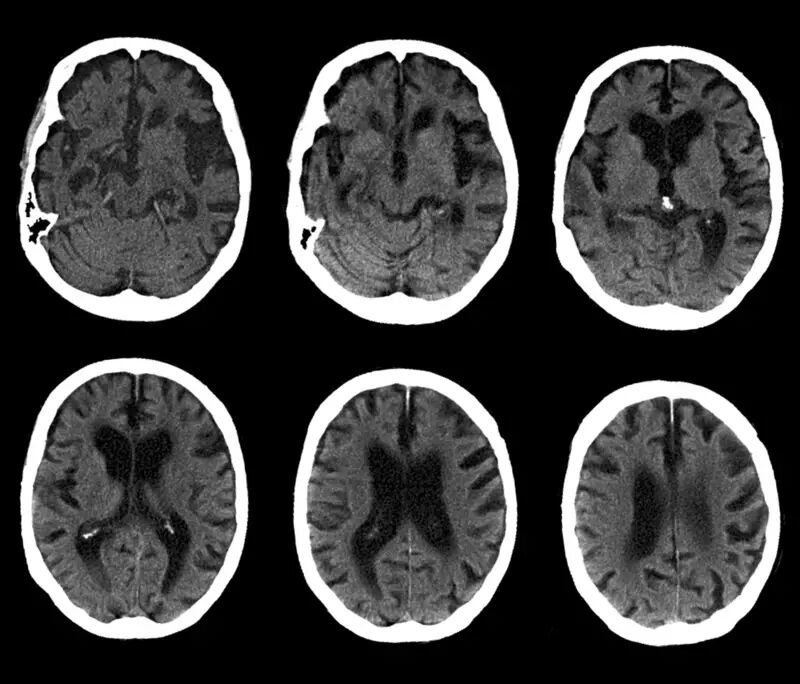

之所以会这样,主要还是因为我们对大脑的认识仍然具有相当大的局限性。我们能够发现头部撞击或者脑部炎症与器质性的精神疾患之间的因果关系,但尽管有了不少脑部扫描的手段和技术,我们对于功能性的精神病患与大脑的因果关系,了解仍然是间接的。

我们可以通过仪器,看到脑的结构,看到脑的活动,但我们很难看见神经元之间的电化学交流——譬如神经突触的受体多少、神经递质的活动水平等等。而这些看不到的事实,很可能才是精神疾患的生理机制。